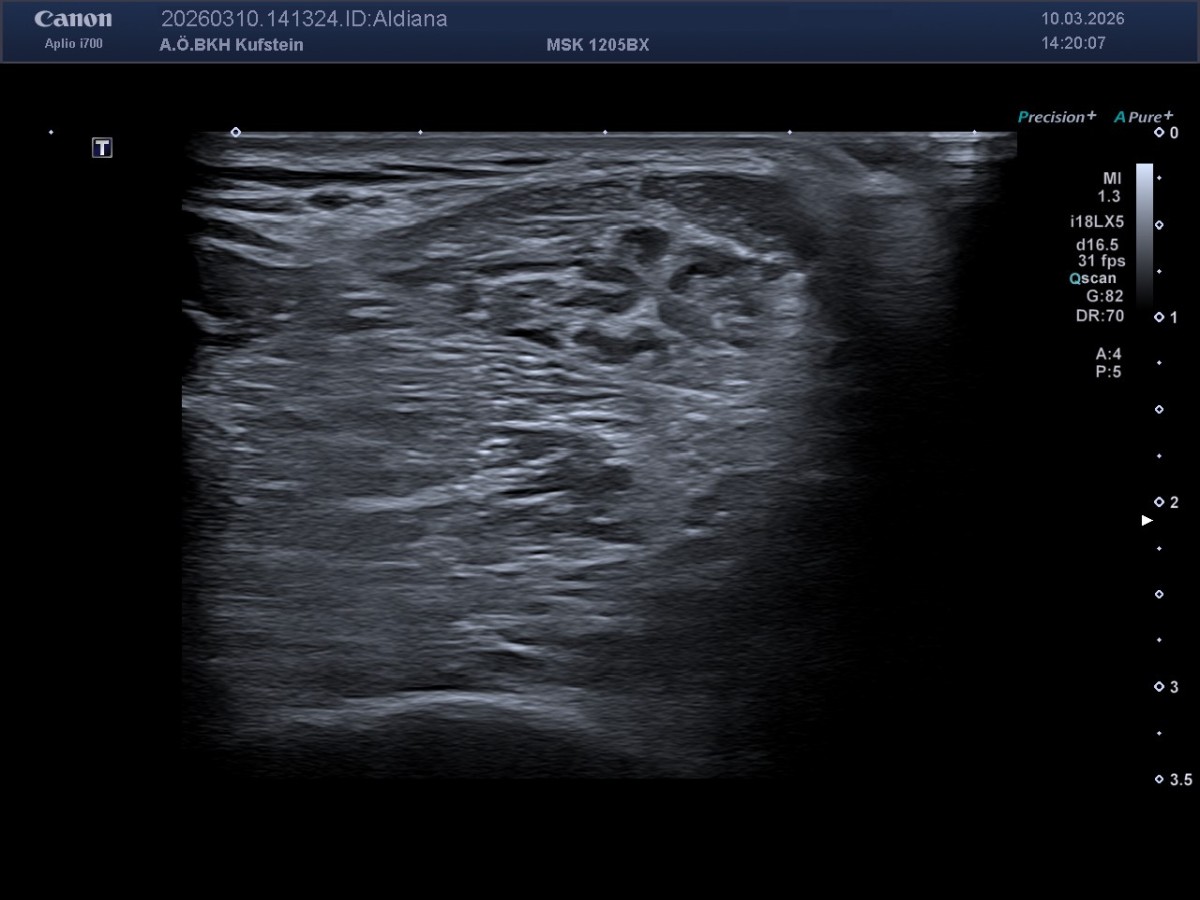

Die MedETeCh Gruppe der diesjährigen siebten Klassen besuchte am 10. März 2026 mit Frau Prof. Mag. Enthofer und Herr Prof. Mag. Dr. Zwicknagl die Abteilung für Radiologie im Krankenhaus Kufstein, um ihr medizinisches Wissen in der Praxis auszutesten. Oberarzt Dr. Martin Neururer, Radiologie-Technologe BSC Robert Nußbaumer und Dr. Paul Peyrer hießen die Schüler*innen in der Radiologie willkommen und unterstützten sie bei ihren ersten Ultraschallversuchen. Nieren, Leber, Milz, Herz, Carotis und Achillessehne konnten von den Schüler*innen eigenständig lokalisiert und anschließend auf dem Bildschirm sichtbar gemacht werden. Die Schüler*innen bedanken sich herzlich beim Team des BKH Kufstein für die freundliche und kompetente Betreuung und die Möglichkeit, selbst aktiv zu werden.